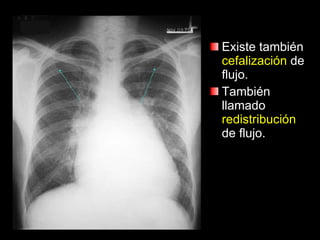

Existe también  cefalización  de flujo. También llamado  redistribución  de flujo.